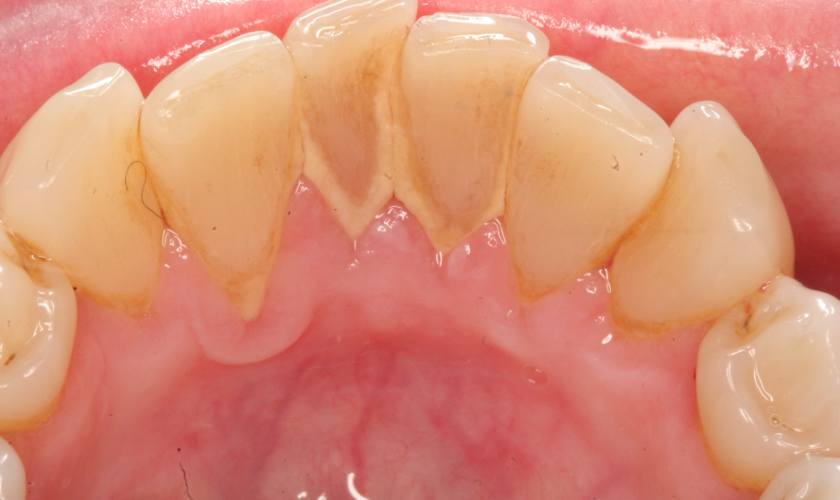

Hiểu đơn giản thì vôi răng chính là mảng bám răng bị đông cứng lại do các thành phần khoáng chất có trong nước bọt.

Vôi răng bao phủ bề mặt răng, lắng đọng giữa các kẽ răng, bên dưới đường viền nướu, có màu vàng hoặc nâu. Vôi răng cứng và bám chặt vào răng, do đó việc loại bỏ vô cùng khó khăn, cần được thực hiện chuyên nghiệp tại các phòng khám nha khoa.